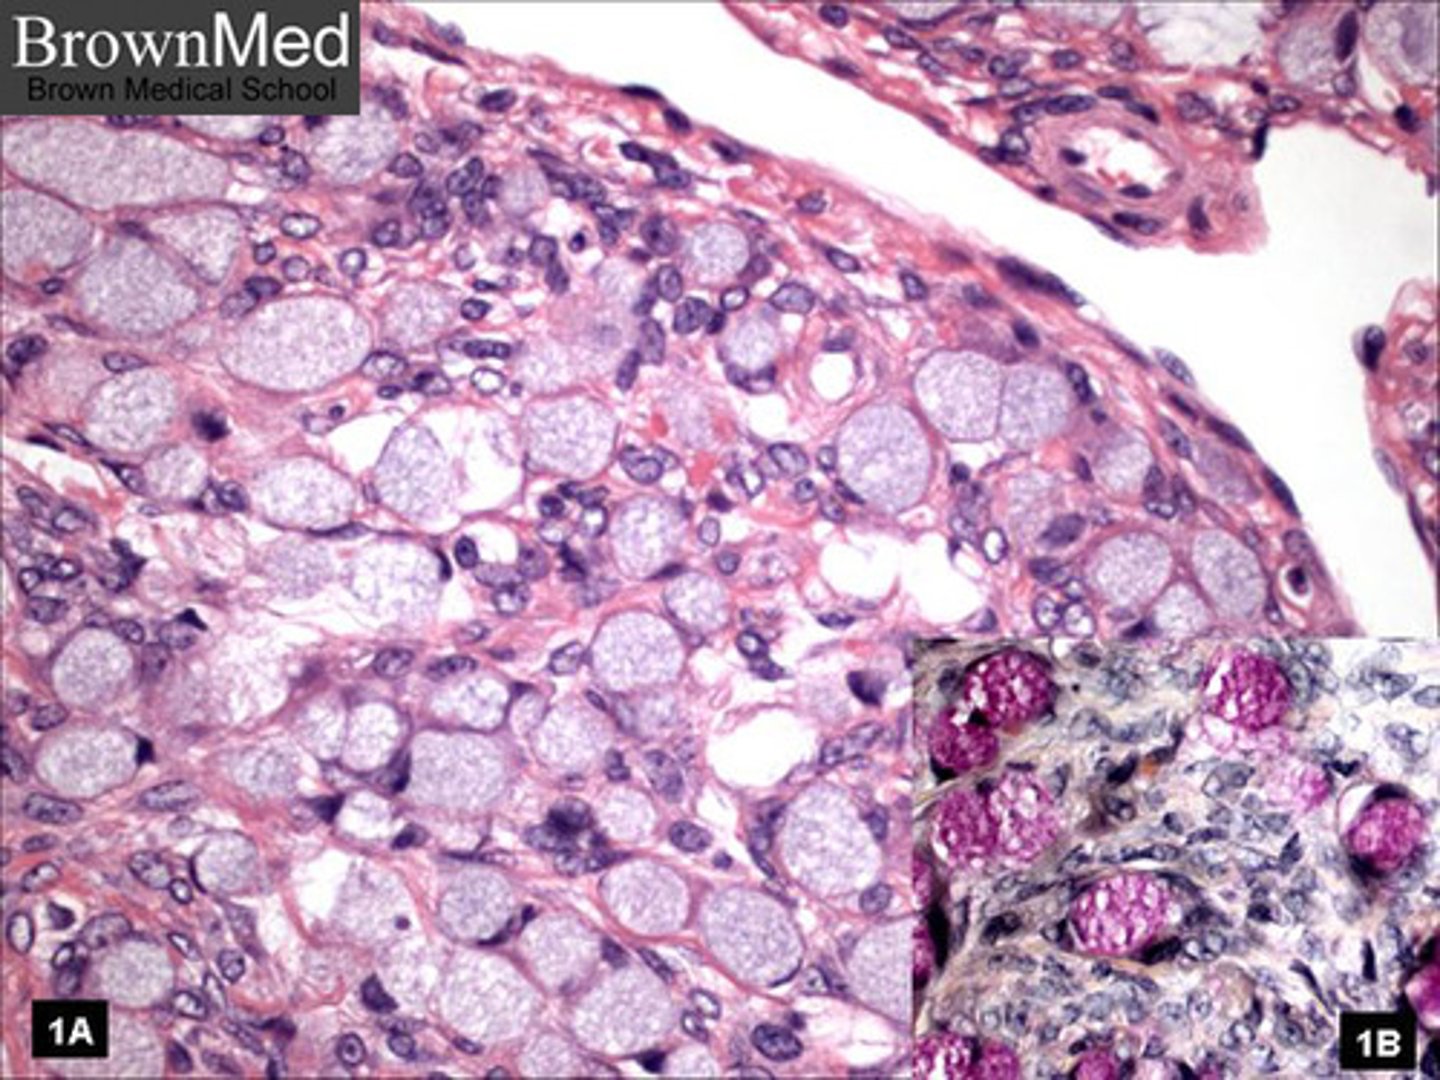

adipose tissue